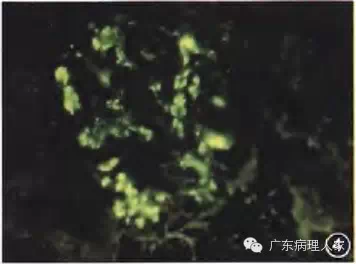

肾活检病理检查方法与一般病理学相比,也有其特殊性:肾穿刺标本体积较小,肾脏的结缔组织较少,光镜标本应该用4%中性甲醛或冰乙酸和乙醇(FAA)混合固定液,以免组织变脆,并为进行免疫病理学检查时多保留抗原;免疫荧光标本应以生理盐水低温条件下保持湿度;电镜标本应以3%戊二醛短期固定。肾活检病理检查需要免疫病理学、光学显微镜(光镜)和电子显微镜(电镜)的综合检查,各有不可替代的作用,缺一不可。(1)免疫病理学检查:很多肾脏疾病由于变态反应引起,与非变态反应肾疾病的治疗方法截然不同,所以肾活检病理检查必须进行免疫病理学检查,常用的方法是应用信誉好的试剂公司的荧光标记的抗体和补体,通过直接或间接免疫荧光法,观察肾组织内有无相应的抗原和补体,并作出半定量诊断,根据荧光显微镜下的荧光强度,分为(-)至(++++),这一点很重要,如+和+++的IgA的意义是不同的(图4)。免疫组织化学方法用于肾恬检病理诊断有一定缺陷,首先,肾小管上皮细胞具有大量线粒体,可产生较多的内源性生物素和内源性过氧化物酶,尽管可通过过氧化氢消除内源性过氧化物酶,但由于内源性生物素的干扰,仍有背景颜色过深的弊端,干扰对于阳性结果的判断。此外,由于肾活检病理需要阳性的定量结果,而免疫组织化学的人为干扰因素较多,不利于定量诊断,所以,肾活检病理的免疫球蛋白和补体的检查以荧光法较受推崇。不过,免疫组织化学法在观察肾活检标本时,在显示特殊细胞和特殊蛋白方面仍有不可替代的作用,如肿瘤细胞的浸润、轻链蛋白的产生部位等。(2)光镜检查:肾活检病理诊断很重视肾内细胞的增生程度、分布状态、细胞种类。与普通诊断病理学相比,肾活检病理检查的标本切片不能太厚,超过3μm的切片可造成细胞重叠,易使增生不明显的肾小球误诊为增生严重的病变。在染色方法和种类方面,不但要行HE染色,还要常规进行过碘酸雪夫(PAS)染色,过碘酸六胺银(PASM)染色和Masson三色染色,以便细致地观察肾小球毛细血管基底膜病变及根据细胞的位置辨认细胞的种类,并根据显色的特点判断特殊蛋白的沉积。各种特殊染色也很必要,如怀疑淀粉样变性肾病必须行刚果红淀粉样蛋白染色,怀疑脂蛋白沉积,应进行苏丹Ⅲ或油红0染色(图5),出现苏木精阳性的沉积物,应作铁、钙特殊染色等。(3)电镜检查:肾活检病理检查中常用透射电镜检查,有时根据需要也可进行扫描电镜和免疫电镜检查。电镜检查用于肾活检病理诊断根据需要可划分为三个层次:①必不可少的、决定性或修正性诊断作用,即不作电镜检查无法诊断或不能正确诊断的肾脏疾病。如一些遗传性肾脏疾病,免疫病理学检查阴性,光镜检查病变不明显,只有电镜检查方可作出诊断,包括薄基底膜肾小球病、Alport综合征(图6)、Fabry病、指甲-髌骨综合征、Ⅲ型胶原肾病、纤连蛋白肾病、脂蛋白肾病等。一些代谢异常、特殊沉积物肾病或早期免疫复合物介导的肾病,光凭免疫病理学和光镜检查很难做出正确诊断,包括早期淀粉样变性肾病、早期糖尿病肾病、冷球蛋白血症肾病、轻链蛋白沉积肾病,纤维样肾小球病、免疫触须样肾小球病等。②具有重要的辅助或参考价值的诊断作用,即凭免疫病理学和光镜检查只能做出初步笼统的诊断,应有电镜诊断验证,包括膜性肾病的分期、膜增生肾小球肾炎的分型,不典型膜性肾病的确诊、新月体性肾小球肾炎的分型、硬化性肾小球肾炎的病因分析等。③与免疫病理学和光镜检查的结果相互印证,保证诊断的正确性。如仅有肾小球上皮细胞足突弥漫融合而无电子致密物沉积,可证实为微小病变性肾小球病或局灶节段性肾小球硬化症;肾小球系膜区大块高密度电子致密物沉积,可证实IgA肾病;肾小球上皮细胞下驼峰状电子致密物沉积,可证实链球菌感染后急性肾小球肾炎;肾小球上皮细胞下电子致密物沉积可证实膜性肾病等。总之,电镜检查是保证正确的肾活检病理诊断的一个必要手段。

图4 IgA肾病,IgA沿肾小球系膜区沉积(++++) 直接免疫荧光 高倍放大